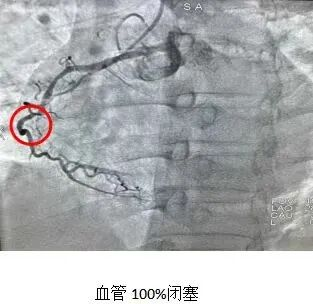

科室开展了先进技术,其中冠脉组常规开展急诊及择期冠状动脉造影及冠脉球囊扩张术、冠脉内溶栓、血栓抽吸术及支架植入术,以及复杂冠脉慢性闭塞(CTO)的介入治疗,术中可行血管内超声、FFR等检查;电生理方向现可开展永久单、双腔起搏器植入、CRT/CRT-D植入、ICD植入以及阵发性室上性心动过速、室早、室速、房速、房扑、房颤等心内电生理检查及射频消融术。在心衰以及高血压方向也与时俱进,积极开展科内业务学习,以新的指南以及专家共识为基石,带给患者最新的以及最合理的治疗方案。